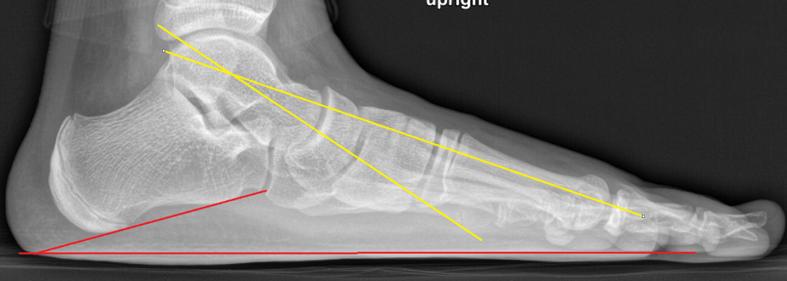

足弓恢复